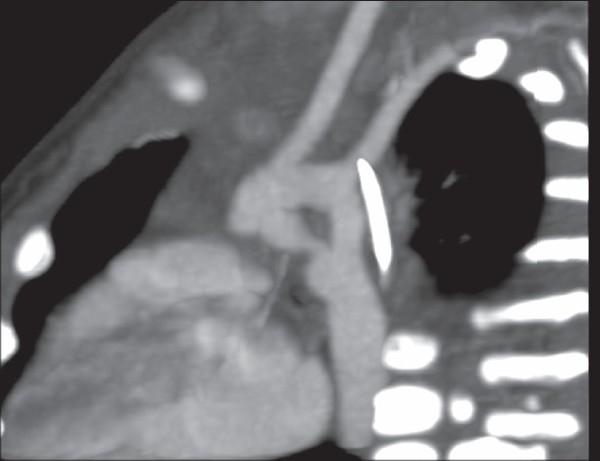

Double aortic arches, esophageal atresia and tracheal compression.

We report a case of double aortic arch in a 12-month-old male infant well delineated on 64 slice computed tomography scan. It formed a complete vascular ring around the trachea compressing it. The symptoms resolved after surgical division of the ring.